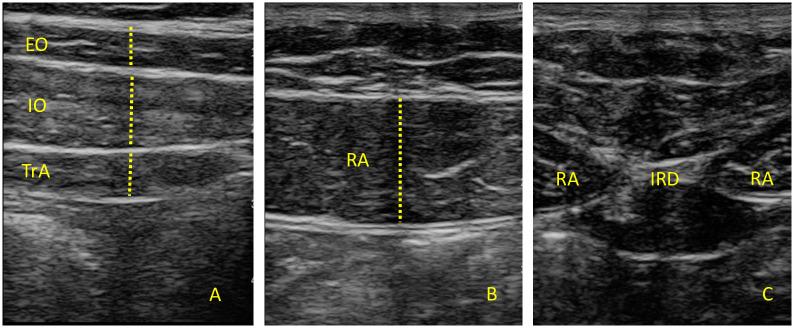

A cross-sectional observational pilot study was performed. A total sample of 24 participants were recruited from a private medical center (Madrid, Spain): Covid-19 (n = 12) and healthy controls (n = 12). The external oblique (EO), internal oblique (IO), transversus abdominis (TrA), rectus abdominis (RA), interrecti distance (IRD) and diaphragm thickness were assessed using USI during inspiration, expiration and during contraction.

USI measurements of the thickness of EO, IO, TrA, RA, IRD and the diaphragm did not differ significantly between groups during inspiration, expiration or during contraction (all P > 0.05).

These preliminary results suggest that the morphology of the abdominal muscles and diaphragm is not altered in people with a recent history of moderate Covid-19 infection.